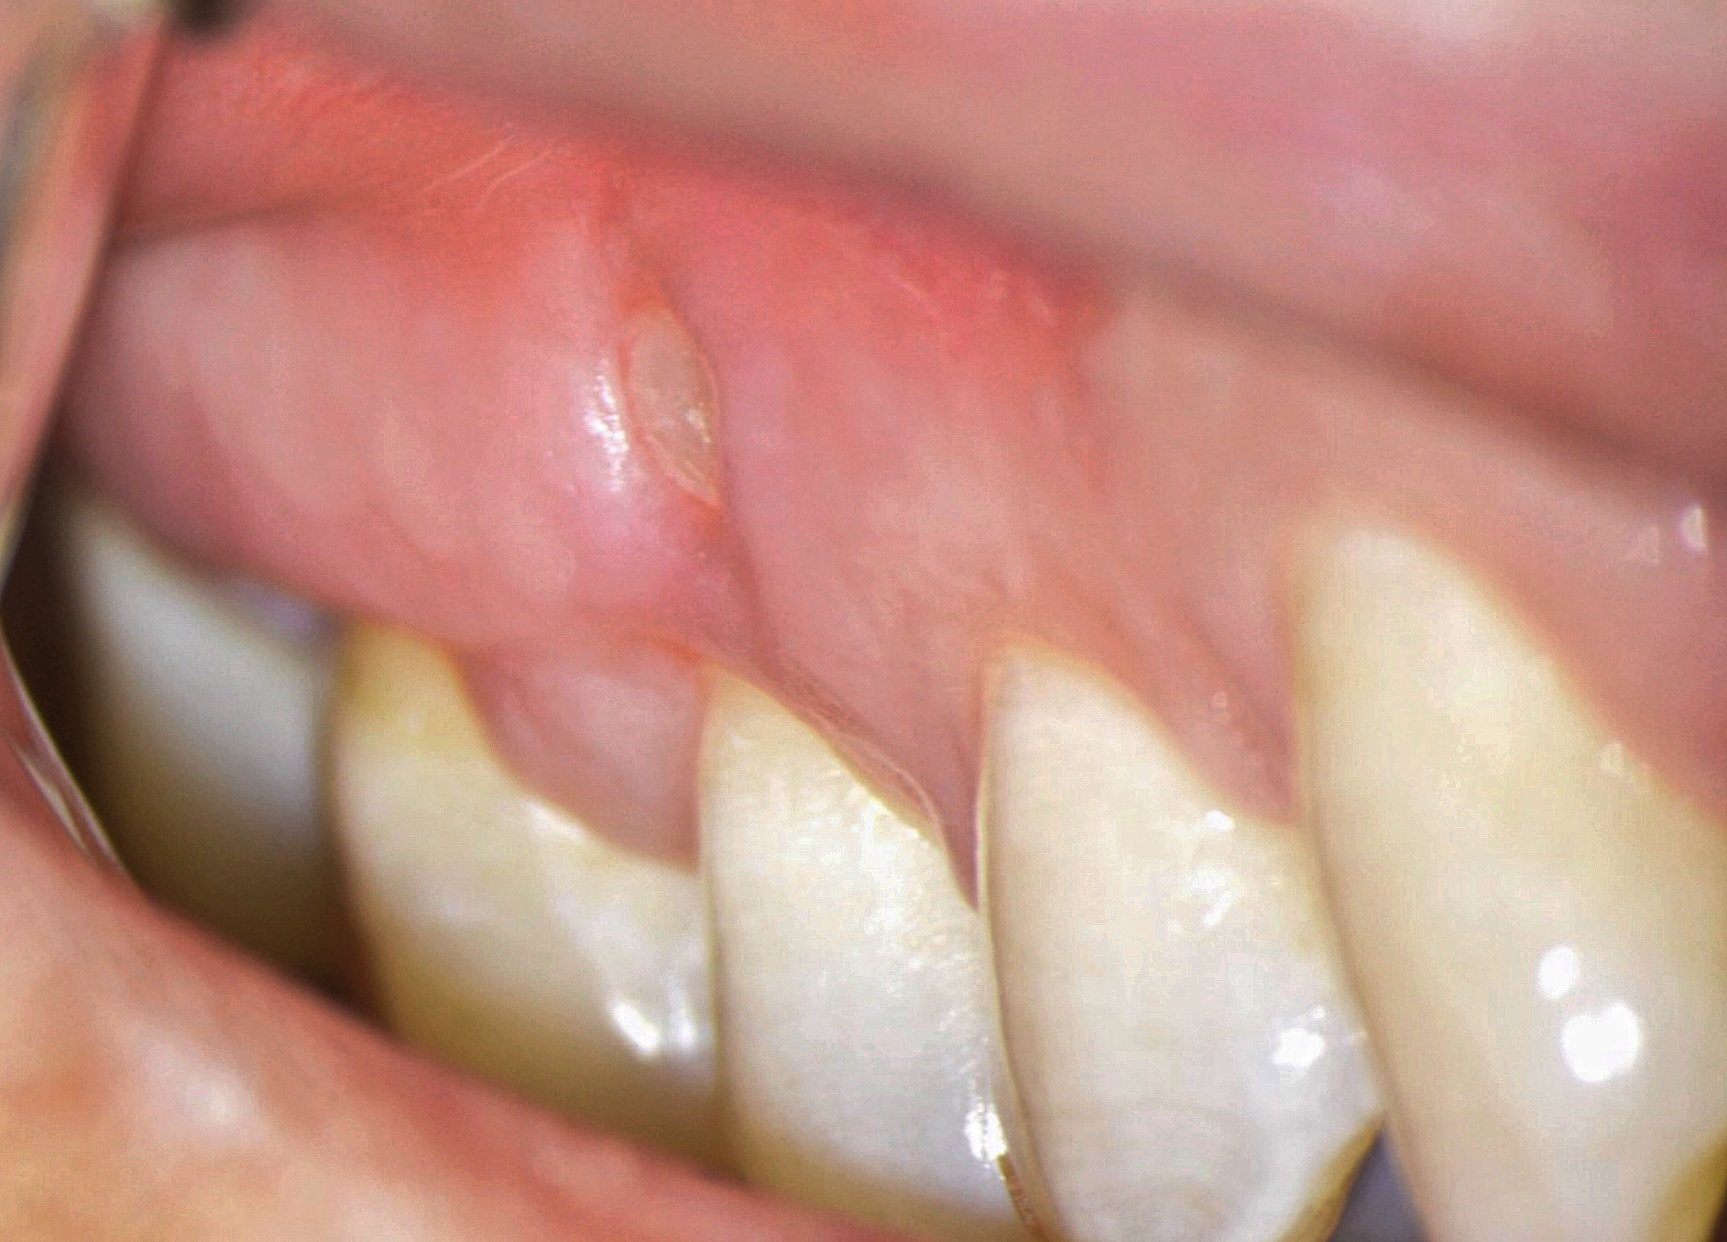

As a consequence of dehydration of the tissue, the Ochsenbein-Luebke flap sometimes tends to shrink during surgery resulting in tension and difficulty in replacing and securing it by suturing. Another disadvantage of the flap described in the literature is the risk of scarring (Fig 14) [7, 30].

According to Lavagnoli and Carnevale (1984), the cause of the scar visible on the attached gingiva is the inclination of the blade to the underlying bone [30]. If the blade is used at 90° to the bone, the incision will involve the epithelium and the periosteum, and the two scars will be superimposed one on top of the other so that they become visible. On the other hand, according to the two authors, if the incision is beveled, the periosteal scar will be covered by healthy epithelium, which will hide the underlying scar. We know today that this is an old theory based on the fact that the periodontists use beveled incisions and they don’t have scars. However, we know today that scarring doesn’t depend on the inclination of the blade, but rather on the correct repositioning of the flap, the precise suturing done under the operating microscope and the early removal of the sutures, as will be described later. In conclusion, the blade can be used at 90° to the bone and by following the above suggestions, there is no risk of scarring [5].

One of the less well-described, rare and late complications of the Ochsenbein-Luebke incision is the occurrence of fenestrations in the soft tissues with baring bone. These fenestrations can be located both in the area of ​​the attached gingiva, which corresponds to the horizontal component of the incision (Fig 15), and on the transition of attached gingiva into the alveolar mucosa, which corresponds to the vertical component of the incision (Fig 16).

The development of soft tissue fenestrations with associated bone exposure is predominantly linked to a thin gingival biotype, suboptimal flap design, and inadequate wound closure.